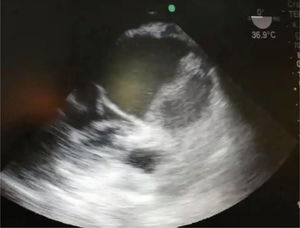

En un control de ecocardiografía, se observa válvula aórtica trivalva, insuficiencia leve y dilatación aneurismática del seno de Valsalva izquierdo. Buena función ventricular. Sin dilatación ventricular (fig. 2).